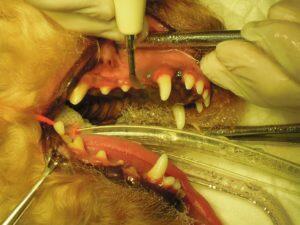

2.左側外観です。